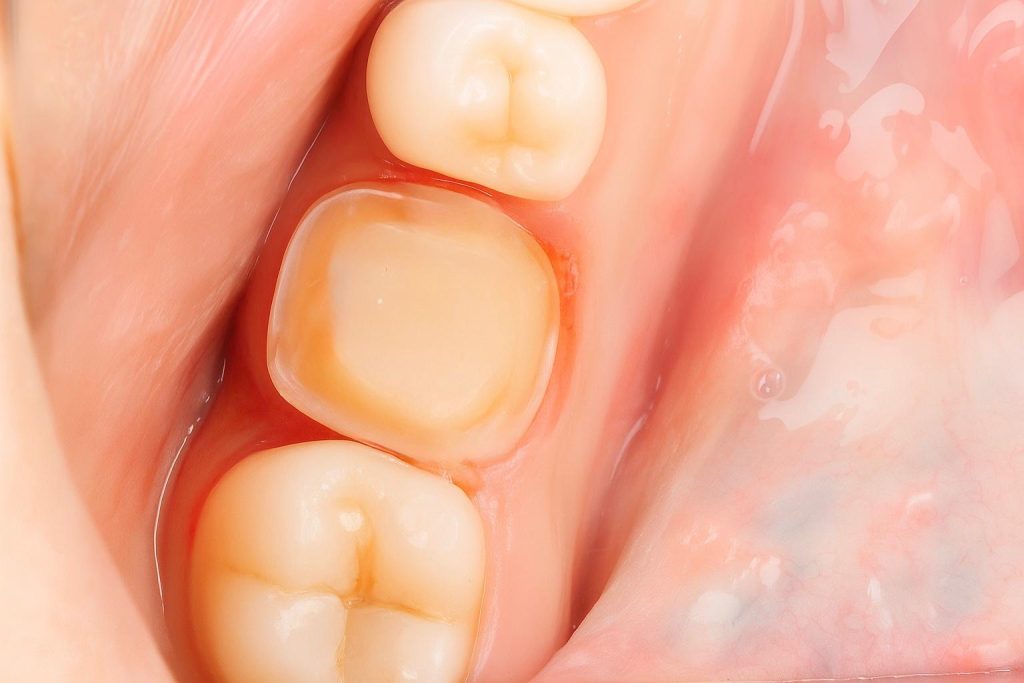

- Tooth prepared conservatively for full coverage.

- Definitive crown fabricated in monolithic zirconia for strength and longevity.

- Bonded with resin cement under isolation.

- Occlusion refined to preserve functional harmony.

Follow-Up – 1 Year

- Soft tissue response healthy and stable.

- Patient asymptomatic, full function restored.

- Restoration clinically intact with excellent marginal integrity.